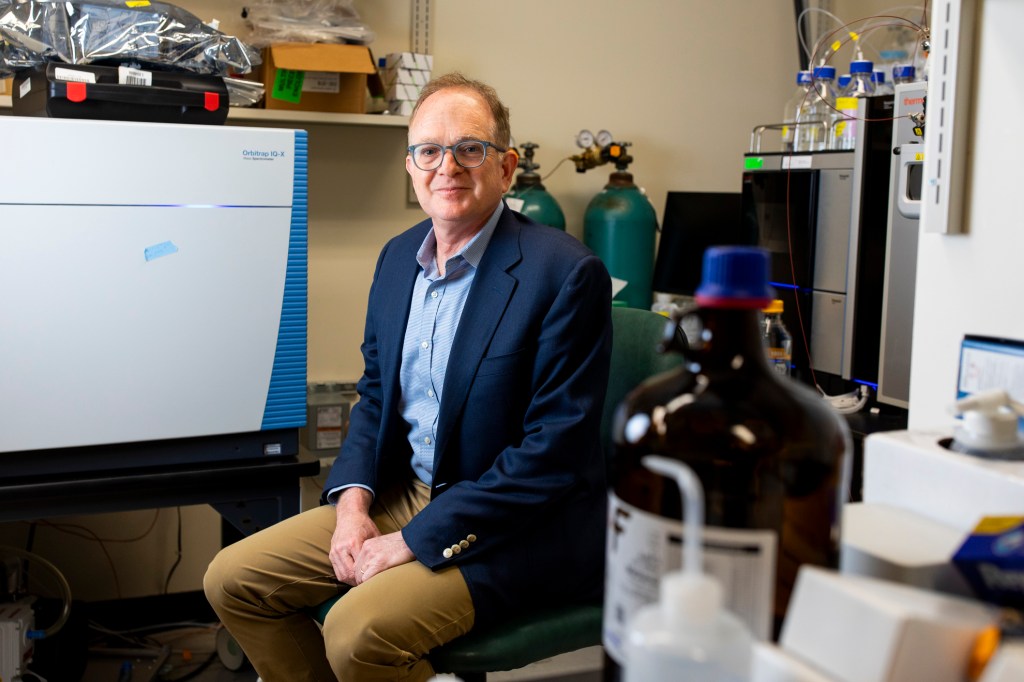

We know exercise is good for you. Why? He‘s working on it.

Expanding on decades of research, a new study seeks to pinpoint movement’s molecular benefits